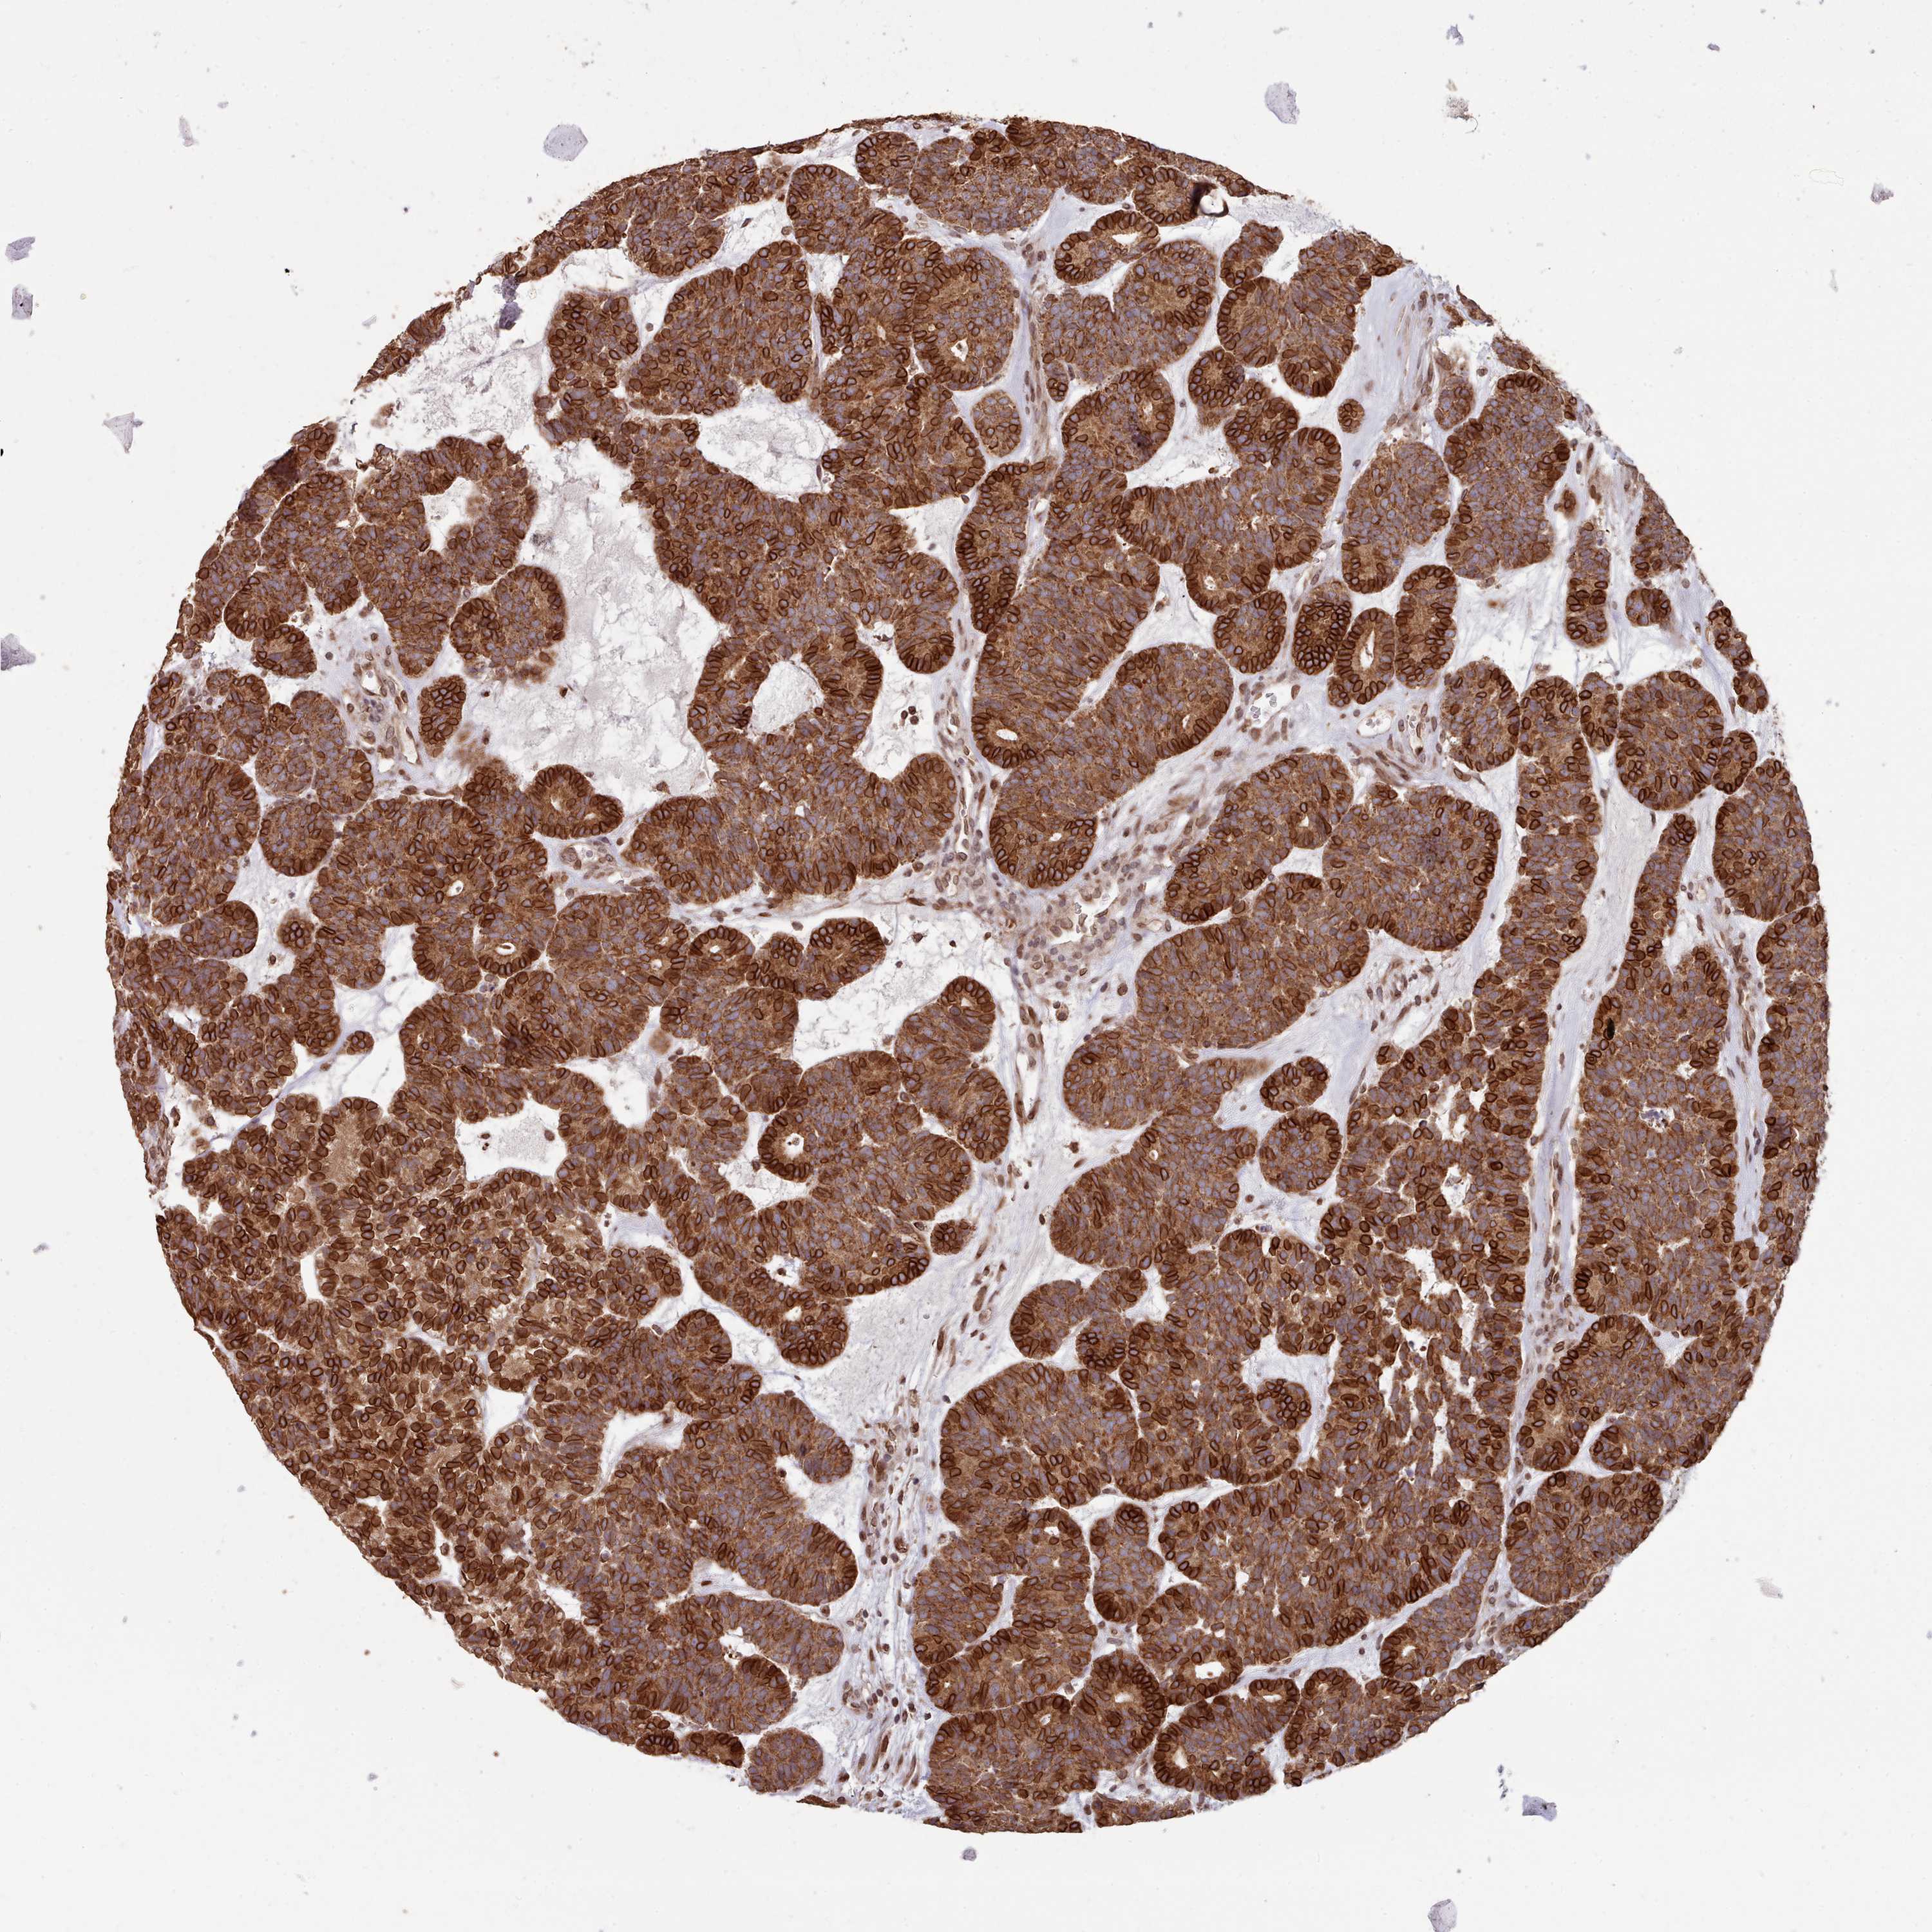

HEAD AND NECK CANCER - Protein expressioni

A mouse-over function shows sample information and annotation data. Click on an image to view it in a full screen mode. Samples can be filtered based on level of antibody staining by selecting one or several of the following categories: high, medium, low and not detected. The assay and annotation is described here.

Antibody stainingi

Antibody staining in the annotated cell types in the current human tissue is reported as not detected, low, medium, or high, based on conventional immunohistochemistry profiling in selected tissues. This score is based on the combination of the staining intensity and fraction of stained cells.

Each image is clickable and will lead to virtual microscopy that enables deeper exploration of all samples and also displays staining intensity scores, fraction scores and subcellular localization as well as patient and tissue information for each sample.

Antibody HPA047151

Antibody HPA050546

Antibody HPA070991

Staining

High

Medium

Low

Not detected

Intensity

Strong

Moderate

Weak

Negative

Quantity

>75%

75%-25%

<25%

None

Location

Nuclear

Cytoplasmic/membranous

Cytoplasmic/membranous,nuclear

Squamous cell carcinoma, NOS

Adenocarcinoma, NOS